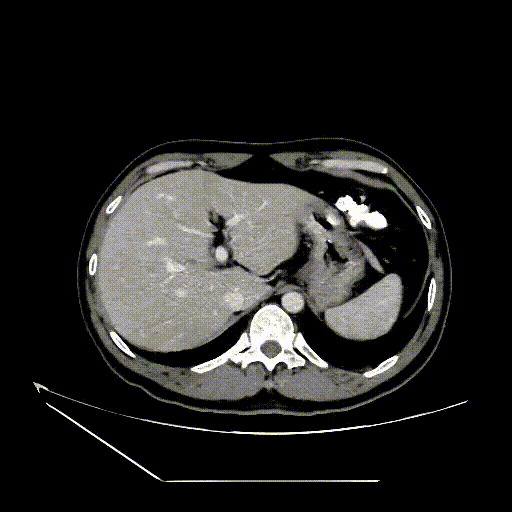

图为:入院CT及增强

图为:CT 三维重建